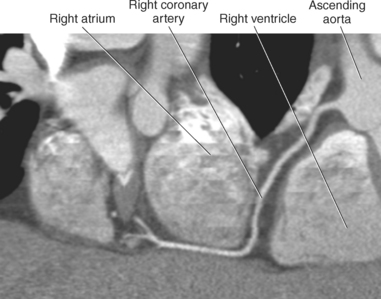

The cardiac muscle requires a continuous supply of oxygen and nutrients, which is supplied by the coronary circulation. The coronary circulation consists of arteries that supply blood to the heart and the cardiac veins that provide venous drainage. The vessels of the coronary circulation frequently vary in their development and distribution of blood to the heart.

The two main coronary arteries are the first vessels to branch off the ascending aorta (Figures 6.91 and 6.92). The right coronary artery arises from the base or root of the aorta (right aortic sinus) and passes anteriorly between the pulmonary trunk and right atrium to descend in the coronary (atrioventricular) groove. As it reaches the diaphragmatic surface, it gives off a right marginal branch that runs toward the apex of the heart. The right coronary artery then turns to the left and enters the posterior interventricular groove, where it gives off the posterior interventricular branch (posterior descending artery). The posterior interventricular branch continues to descend along the interventricular groove toward the apex, where it anastomoses with the left anterior descending artery of the left coronary artery. The right coronary artery and its branches supply the right atrium, right ventricle, interventricular septum, and the sinoatrial (SA) and atrioventricular (AV) nodes. It also supplies a portion of the left atrium and ventricle (Figures 6.92 through 6.96). The left coronary artery arises from the left aortic sinus and passes to the left between the pulmonary trunk and left atrium to reach the coronary groove (Figures 6.91 and 6.92). Soon after reaching the coronary groove, the left coronary artery divides into the circumflex and left anterior descending (interventricular) arteries. The circumflex artery winds around the left border of the heart to the posterior surface, where it gives off the left marginal artery. The left anterior descending artery (LAD) descends in the anterior interventricular groove toward the apex of the heart, where it reaches the diaphragmatic surface to anastomose with the posterior descending artery. The left coronary artery and its branches supply the interventricular septum, including the AV bundles, and most of the left ventricle and atrium (Figures 6.97 through 6.99).